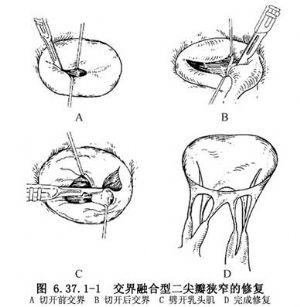

(1)交界融合型:充分切开融合的交界,直至距瓣环2mm为止,瓣下融合的腱索按附着瓣膜边缘分界向下劈开,并劈开乳头肌使其充分舒展(图6.37.1-1)。